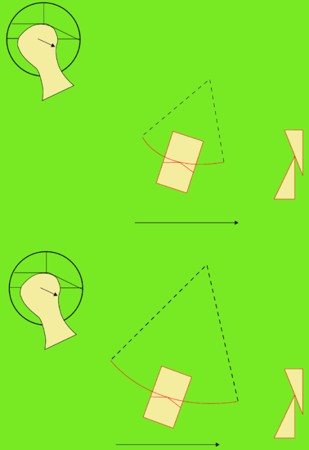

Primera Parte RESUMEN: La alta complejidad inherente a los procedimientos de Rehabilitación Oral, obligan al profesional que la ejerce a basarse en parámetros multidisciplinarios, a veces lo suficientemente intrincados que hacen imposible la práctica de la misma, sin la presencia en su mente de una clara concepción de la Oclusión. The extreme complexity of Oral Procedures, make it imperative for the working professional to rest on multidisciplinary parameters, sometimes so complex that make impossible its practice without the presence of a clear idea of Oclusion. DESARROLLO Suele ser sumamente árido el abordaje de un tema como Oclusión, desde la perspectiva de nuestro diario trabajo ,con todo el strees que este conlleva, con toda la lucha que significan citas, honorarios, diferentes personalidades de los pacientes, inquietudes de los mismos, etc. «LA MEJOR OCLUSIÓN ES LA QUE TIENE LA MEJOR DESOCLUSIÓN» Básicamente, podemos como desde hace ya muchos años se viene haciendo; clasificarlos en: A)Determinantes Posteriores (fijos) Más contemporáneamente, en: I-Mecanismos Primarios: A.T.M. GUIA ANTERIOR INCLINACIÓN DEL PLANO OCLUSAL CURVA SAGITAL DE SPEE FORMA DE LA ARCADA III-Mecanismos Elementales CRESTAS TRIANGULARES INTERNAS Analicemos cada uno de ellos: Es evidente, que la reproducción de las características de la A.T.M., en nuestro aliado fundamental, el Articulador; es imprescindible. Partiendo de la premisa de obtener una OCLUSIÓN MUTUAMENTE PROTEGIDA, para luego arribar al concepto de OCLUSIÓN MUTUAMENTE COMPARTIDA, concepto este que desarrollaremos durante el transcurso de las distintas entregas, analizaremos cada uno de los FACTORES DETERMINANTES DE LA OCLUSIÓN. El primero de ellos, por ser fijo e invariable, solo diremos que: son sus INCLINACIONES PLANARES, o sea : A-INCLINACIÓN DE LA TRAYECTORIA CONDILEA C-BENNET INMEDIATO articuladores totalmente ajustables) D-DISTANCIA INTERCONDILAR. En cuanto a la GUÍA ANTERIOR, mecanismo primario y por supuesto anterior, provee al cuerpo mandibular; del camino a recorrer durante las excursiones protrusivas y lateralidades, a través del vínculo entre las piezas dentarias anteriores, superiores e inferiores. En un corte sagital, podemos observar la relación entre estos donde vemos que se vinculan sin entrar en un contacto franco, sino más bien en una relación de vencindad muy intima a la que llamamos: PUNTO DE ACOPLAMIENTO. Otros factores fundamentales de la GUÍA ANTERIOR son : A-ALTURA FUNCIONAL B-PUNTO DE ACOPLAMIENTO En cuanto a los SURCOS, sabemos que durante una Transtrusión, las cúspides fundamentales generan surcos sobre las piezas que antagonizan. Dichos surcos proveen de una vía de escape a las cúspides antagonistas para evitar colisiones, con las indeseables fuerzas laterales cuya gravedad ya conocemos. MECANISMOS SECUNDARIOS La CURVA FRONTAL DE WILSON, se observa invertida a nivel de los caninos y de los primeros premolares. El PLANO OCLUSAL, en realidad no es ningún plano, sino la sumatoria de muchos MICROPLANOS, los cuales individualmente pueden constituir factores presentes en la OCLUSIÓN, pero auténticos problemas para la DISCLUSIÓN. La CURVA SAGITAL DE SPEE, denominada originariamente de BALKWIL-SPEE, fue concebida como una curva. El cuarto factor SECUNDARIO: el ANCHO DE LA ARCADA, es evidente que variando los ejes de rotación , alrededor de las diferentes distancias ;cambiará la dirección de los escapes (surcos), de los elementos que en el se muevan (cúspides). MECANISMOS ELEMENTALES Los CUATRO NIVELES DE OCLUSIÓN y las CRESTAS TRIANGULARES INTERNAS, constituyen de por si, la herramienta ejecutora de las funciones gnáticas. A- ELEVACIONES 1-Puntas Cuspídeas B-DEPRESIONES 1-Fosas SURCOS DE DESARROLLO De las CRESTAS TRIANGULARES INTERNAS, acentuamos su importancia en ellas dado que son las efectoras finales de la molienda, y su triangularidad debe tener su base partiendo del surco y su vértice terminando en la Punta Cuspídea, condición importante para evitar colisiones durante la transtrusión (movimiento de lateralidad ). EFECTOS DE LA VARIABILIDAD DE LOS FACTORES DETERMINANTES DE LA OCLUSÍON Cada uno de los determinantes influye aumentando o disminuyendo tanto la DESOCLUSIÓN como la ALTURA CUSPÍDEA INCLINACIÓN DE LA TRAYECTORIA SAGITAL INCLINACIÓN DEL PLANO OCLUSAL RADIO DE CURVATURA DE LA ÁNGULO DE LA TRAYECTORIA ALTURA DEL PUNTO DE LATERO SURTRUSIÓN / MOV. DE BENNET INMEDIATO CURVA FRONTAL DE WILSON SURCOS BIBLIOGRAFÍA Dibujos y esquemas tomados del libro: Oclusión Orgánica…un camino hacia la Rehabilitación Oral. 1)William Mc Horris,B.S.,D.D.S. Oclusión. Con especial énfasis sobre :El rol funcional y parafuncional de los dientes anteriores. 2)Von Spee , Craff(Anatomista alemán, describió la curva de compensación de la articulación de molares y premolares).CURVA DE SPEE 1.89 3)Stuart,D.»Some aspects of the inervation teeth.»Procedings of Royal Society of Medicine.20:1675,19274)Muhleman,H. y Savdir,S»Tooth movility-its causes and significance»Journal of Periodontology ,36:153,Marzo ,Abril,1965. 4)Muhleman,H. Y Savdir,S»Toothmovility its causes and significance» Journal of Periodontology,36:153,marzo,abril,1965. 5-Oclusión y Diagnóstico en Rehabilitación Oral. 6-Anatomia Odontológica. -A contribution to the study of the movementes of the mandible. 8-Celenza F.W, Nadeskin J.F.,Oclusión.Situación actual. 9-D´Amico 10-Dawson P.E. 11-Huffman -Regenos. 12-Hobo S.-Takayama H.A. 13-Lucia V.O 14-Mc Horris. 15-Mc Horris. 13-Posselt U. 16-Stuart C. 17-Vartan Veshnilian

Ahora bien, como; la variabilidad de cada uno de estos factores influye sobre nuestros patrones oclusales, es una cuestión a desmenuzar:

CURVA SAGITAL DE SPEE

A menor radio, mayor altura cuspídea, mayor desoclusión.